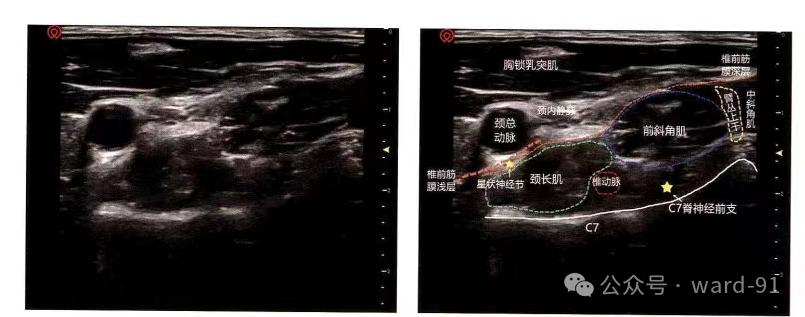

星状神经节位于C7横突根部和第1肋骨颈前面,椎动脉和锁骨下动脉后方,气管、食管和颈长肌的外侧,肺尖的上方

将高频探头横切置于C7 横突切面,Mark朝向内侧

| 骨骼 | C7横突后结节 |

| 肌肉 | 胸锁乳突肌;颈长肌和前斜角肌 |

| 筋膜 | 椎前筋膜浅层和深层 |

| 血管 | 颈总动脉;颈内静脉;椎动脉 |

| 神经 | 星状神经节; |